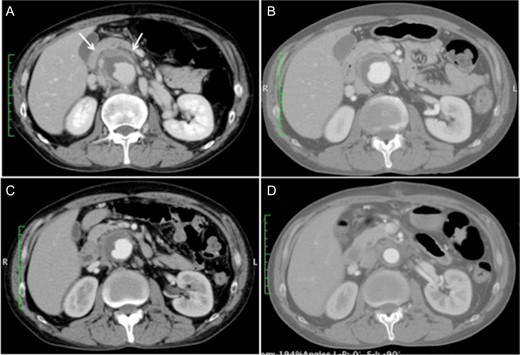

Upon admission, the patient’s blood pressure was 135/72 mmHg, and he had low-grade fever at 37.4°C. Blood analyses showed a nearly normal level of white blood cells but elevated C-reactive protein of 20.1 mg/dL. Contrast-enhanced CT of the abdominal vessels showed a juxtarenal AAA (maximum diameter, 50 mm) surrounded by dense perianeurysmal fibrous tissue (Fig. 1A). Despite repeated cultures, the causative microorganism was not identified. The clinical presentation and imaging findings led to the diagnosis of a symptomatic IAAA. To control the perianeurysmal inflammation, steroid therapy with prednisolone was initiated at a dose of 30 mg/day, which was gradually reduced to 10 mg/day using inflammatory signs and change in the size of retroperitoneal mass as a reference (Fig. 1B and C). He responded well to steroids initially and his abdominal pain resolved. The patient underwent elective surgery 21 days after commencing steroid therapy.

(A) Contrast-enhanced computed tomography scan at the time of admission showing a 50-mm juxtarenal abdominal aortic aneurysm surrounded by dense fibrous tissue (white arrows). (B and C) The perianeurysmal fibrous tissue became smaller along with the course of steroid therapy, 7 and 14 days after the initiation of steroid therapy, respectively. (D) Postoperative computed tomography scan showing a patent graft with near disappearance of the fibrous tissue.

He recovered uneventfully, and postoperative contrast-enhanced CT revealed a patent graft and a decrease in the retroperitoneal mass (Fig. 1D). Histopathologic examination demonstrated excessively thickened tunica adventitia with infiltration of inflammatory cells such as lymphocytes and fibrosis (Fig. 3). The patient was discharged without subjective symptoms on postoperative Day 10.